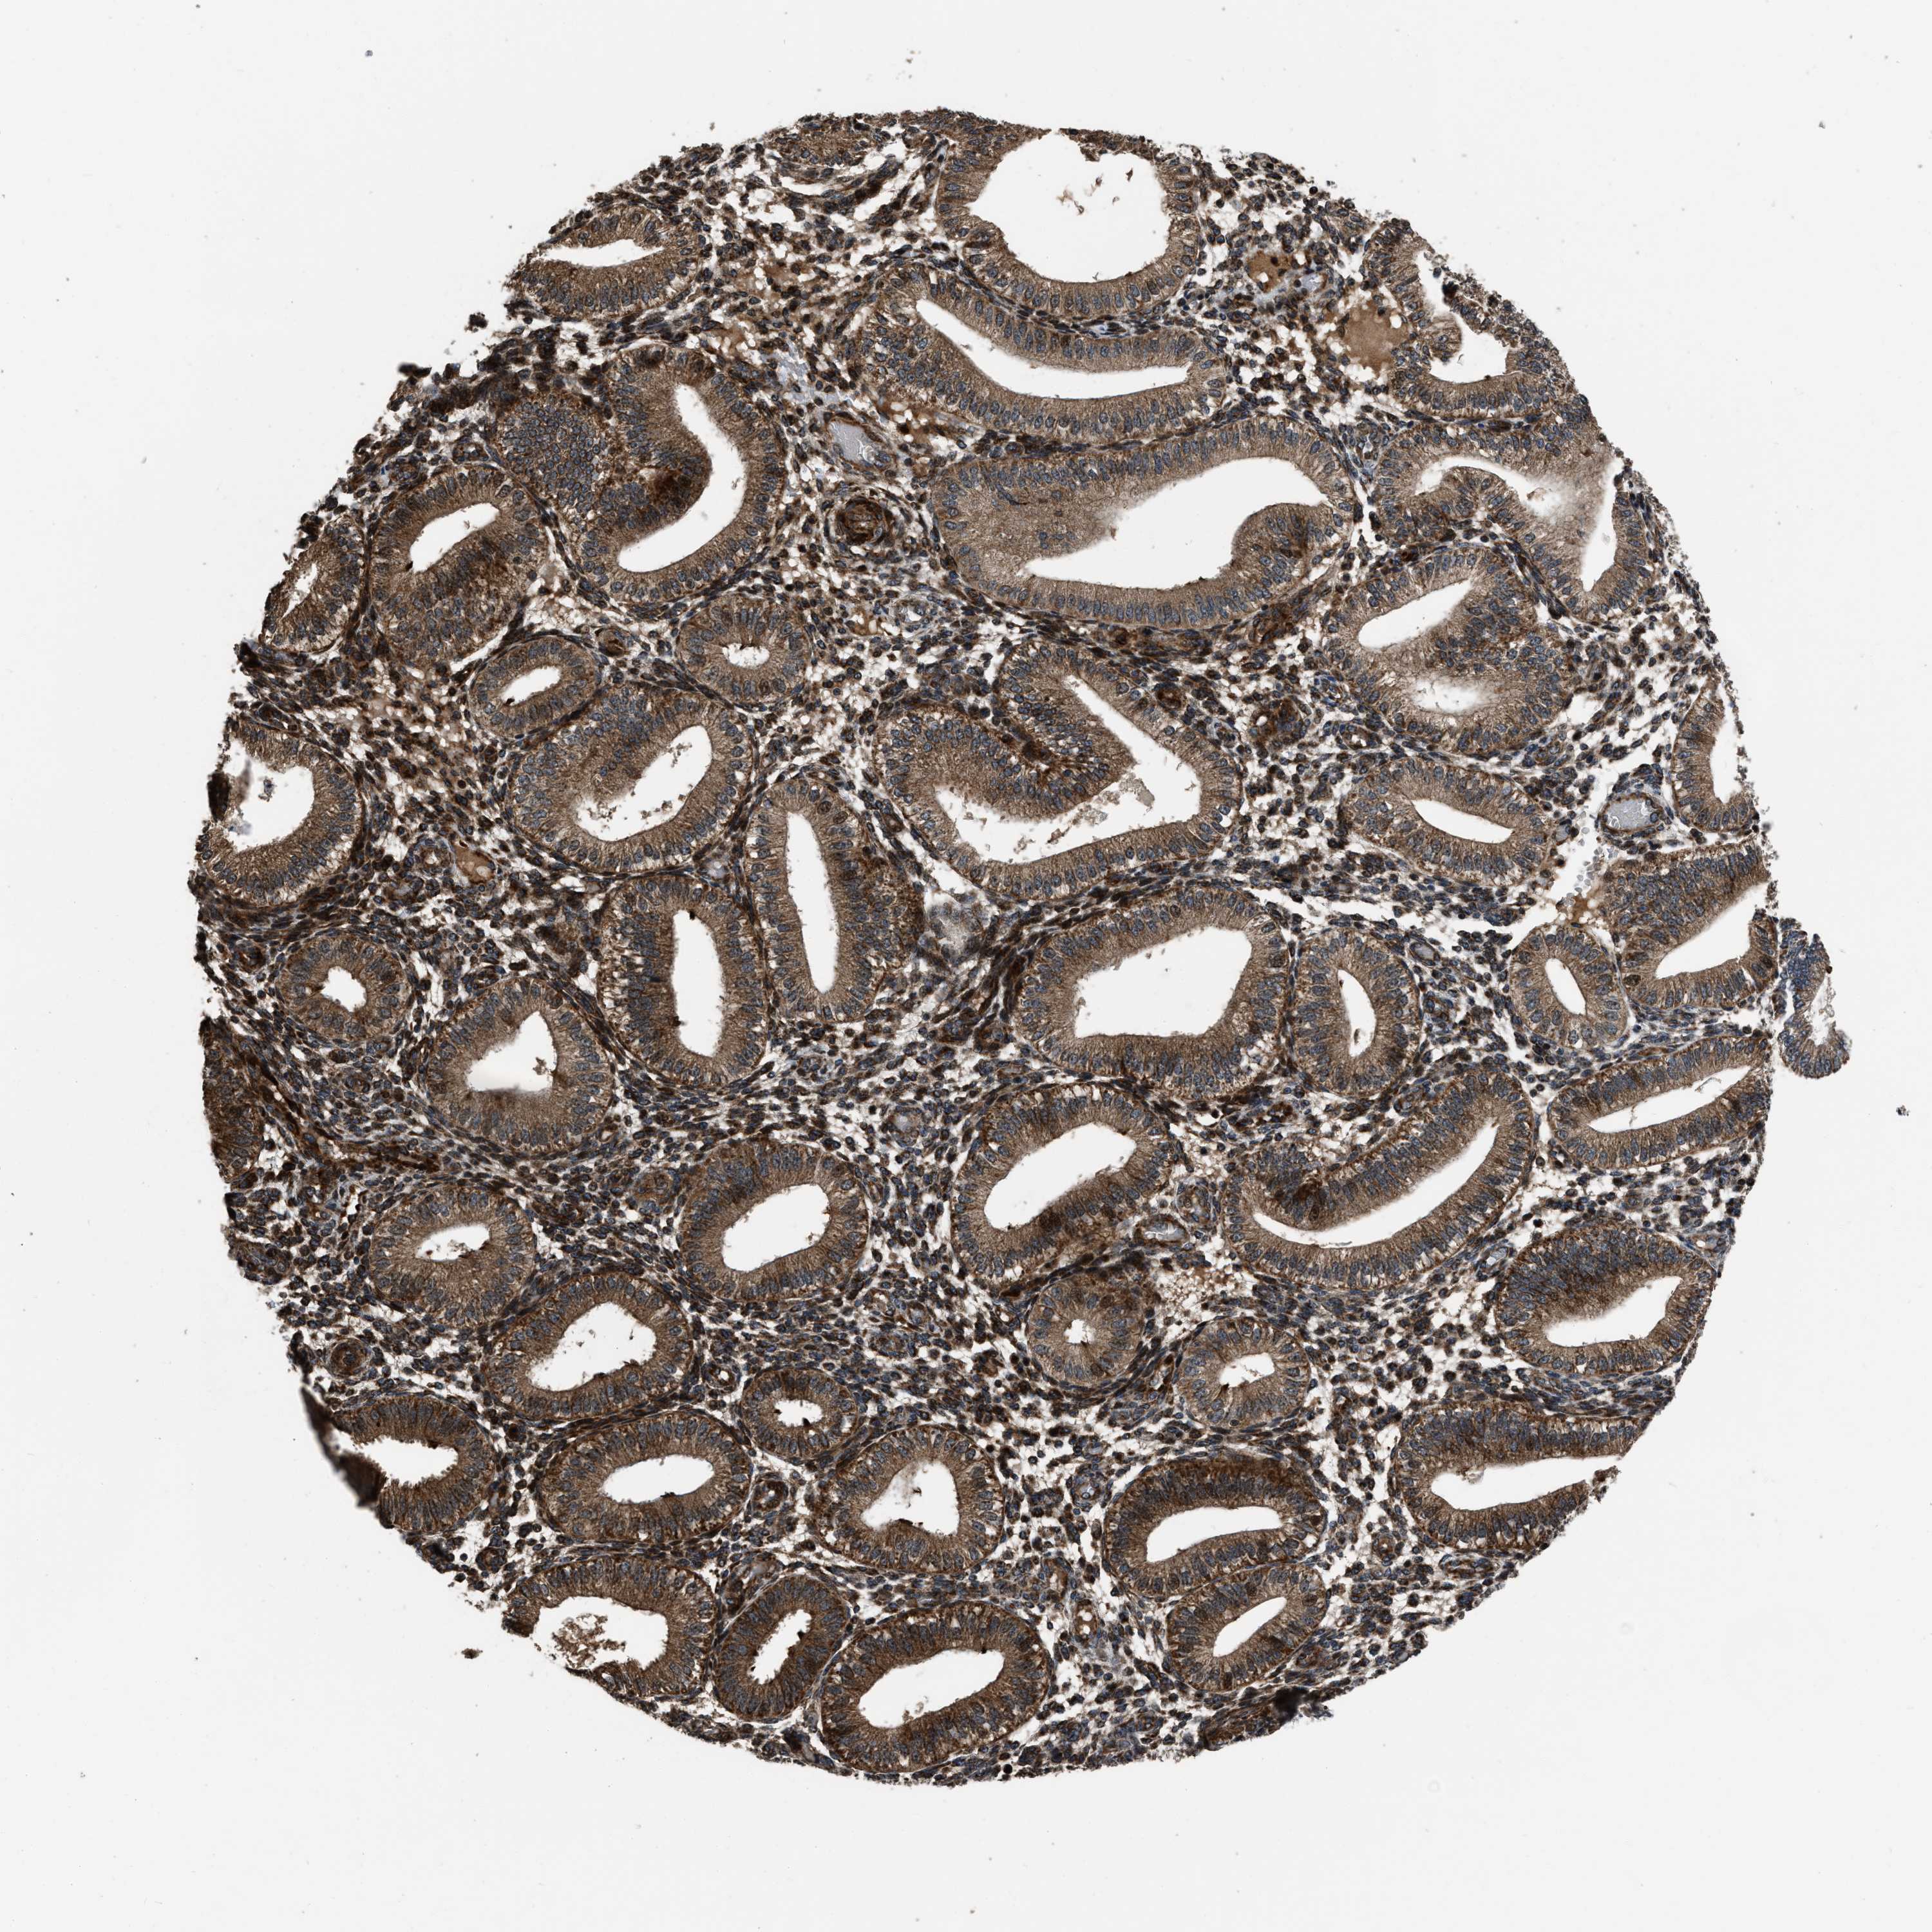

NSD3